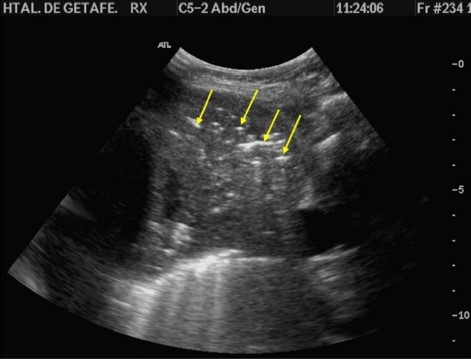

Las consolidaciones pueden ser translobares o no translobares. La mayoría son de esta última forma, y el signo que las representa es el signo del fractal (o de la scie o dientes de sierra) (figura 10): la zona limítrofe entre el tejido consolidado y el aireado normal se vuelve irregular, con “tiras” o bordes irregulares o “rasgados”. Para que se produzca este signo debe haber tejido aireado (por eso se produce en condensaciones no-translobares, parte del lóbulo pulmonar donde está la condensación debe estar preservado para que se produzca la interfaz aire-condensación).

En neumonías translobares, que ocupan un lóbulo entero (o más), NO puede haber signo del fractal ya que el tejido no está aireado (está todo condensado, o sea, con líquido). Y por lo mismo, el parénquima pulmonar comprometido toma la densidad de otros tejidos: es el signo del tejido o tissue-like, o “hepatización”, ya que el parénquima comprometido termina pareciéndose mucho al parénquima hepático (figura 11).

Resumen del síndrome de condensación: Principal compromiso en el punto PLAPS. Signo del fractal, signo del tejido, engrosamiento pleural, broncograma aéreo dinámico.

| El signo del límite irregular («shred sign»), (o de la scie o dientes de sierra) | «Tiras» o bordes irregulares desde la pleura. Se produce cuando hay consolidación subpleural, o consolidación no-translobar (ej. Neumonía). |

| Signo del tejido (tissue-like) | El pulmón obtiene una densidad similar al hígado (“hepatización”). Se observa en consolidación translobar (neumonía). |